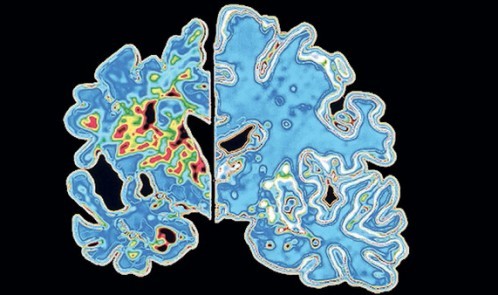

تا کنون، شرکت الی لیلی رسما در مورد نتیجه تحقیقات پیرامون کارآیی این دارو اظهار نظری نکرده است اما پژوهشگران این شرکت در اجلاسی که اخیرا برگزار شده بود گفتند که نتیجه به دست آمده از ٢٨ هفته درمان نشان می‌دهد که بیمارانی که در مراحل اولیه ابتلا به آلزایمر تحت معالجه قرار گرفتند توانایی ذهنی خود را در حدی بازیافتند که در بیماران قدیمی‌تر مشاهده نمی شد.

به گفته آنان، این نتیجه نشان داد که استفاده از این شیوه درمانی روند بیماری را به شکل قابل توجهی تغییر داده است.

شمار دیگری از موسسات تحقیقاتی نیز از موفقیت در یافتن روش‌های تشخیص علایم اولیه بیماری زوال عقل، حتی تا ده سال قبل از بروز نخستین عوارض آن، سخن گفته‌اند اما اگر شرکت ایلی لیلی در گزارش روز چهارشنبه خود، از موفقیت در آزمایش شیوه درمانی جدید روی مبتلایان به آلزایمر خبر بدهد، باید آن را نقطه عطفی مهم در مسیر درمان این بیماری دانست.

در حال حاضر، میلیون‌ها نفر در جهان به بیماری آلزایمر مبتلا هستند. شمار مبتلایان در بریتانیا به حدود ۸۵۰ هزار نفر می‌رسد و هر ساله دست کم ۶۰ هزار نفر در اثر این بیماری جان خود را از دست می‌دهند.